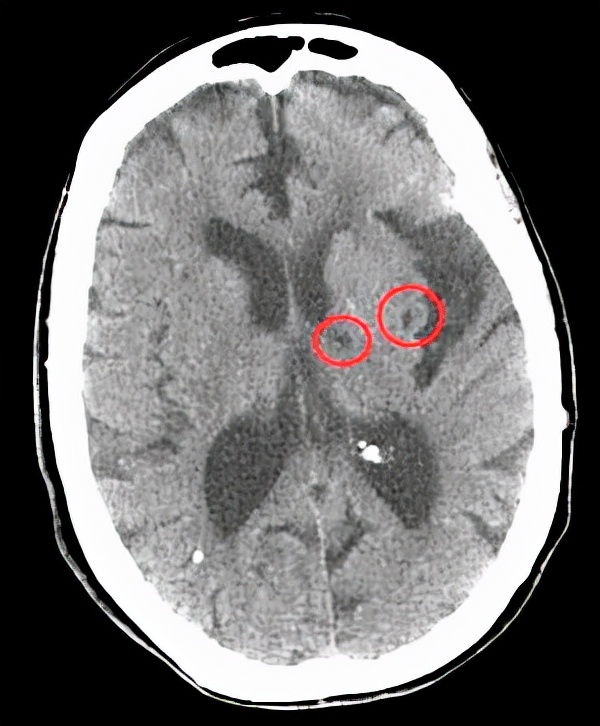

一、脉络丛钙化。

在报告单上经常可以看到脉络丛钙化这个名词,很多人一看:脑子里面有钙化了,一定是不好的东西。

真是这样吗?其实并不用害怕,脉络丛钙化可能并没有什么问题,只是你的大脑血管有些老化而已。

脉络丛其实是一束血管,通常来说是软脑膜以及在软脑膜中穿行的血管,和其他组织共同所组成的,这类组织最主要的特点就是有血管在里面穿行。

所以把它视为“一束血管”,可能会比较恰当。

而随着年龄的增长脉络丛可能出现钙化,通常都是生理性的,并不需要太在意。

另外也要看具体情况,有没有其他的症状体征,如果什么问题都没有,一般是不需要处理的,也不需要用药。

但是如果有症状呢,身体真的感觉不一样了,脉络丛钙化可能也预示着某些肿瘤的出现,甚至和脑积水也相关,这个时候就不要轻易放过了。

总之具体情况具体分析,不能以偏概全,也不要吓唬自己。